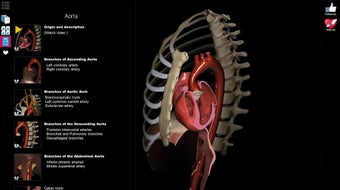

Anatomy Learning - 3D Atlas è un'app gratuita per Android che appartiene alla categoria Medicina ed è stata sviluppata da AnatomyLearning. È consigliata per principianti, studenti di medicina, apprendisti visivi, professionisti medici, medici.

Questa app è meglio conosciuta per le seguenti caratteristiche e qualità: strumento di studio, apprendimento dell'anatomia, strumento di apprendimento e riferimento di base.